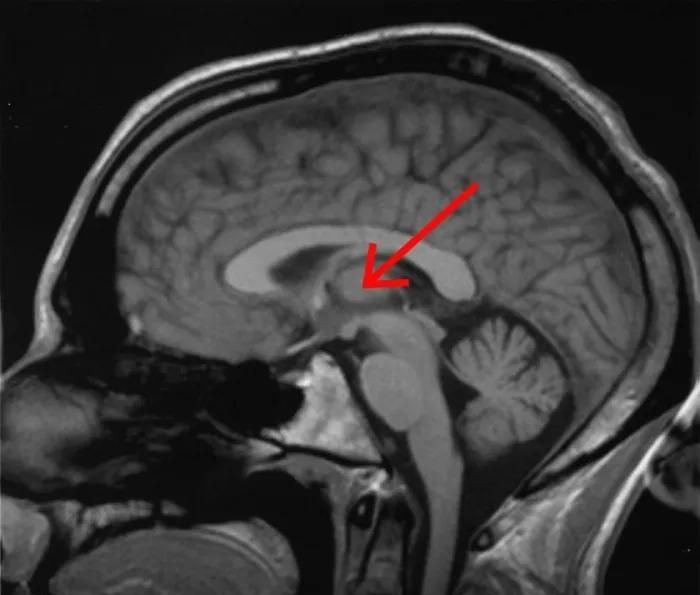

虽然意识的诞生过程,尚且停在假说阶段,但研究人员极有可能已经找到了意识的开关——中央外侧丘脑。

威斯康星大学麦迪逊分校的研究人员发现,使用50 Hz电刺激中央外侧丘脑时,处于麻醉状态的猕猴能够苏醒,并出现正常的清醒行为。

猴子睁开眼睛,生命体征出现变化,面部和身体开始运动,并伸手去拿附近的物体。

不过,关闭电刺激之后,仅仅几秒钟,猴子便会再次闭上眼睛,回到无意识的状态。

上述实验,必须超级精准才能实现。

50 Hz的电脉冲,只能点击仅仅20纳米的特定位置。

这表明,中央外侧丘脑对意识具有必定的启动作用。